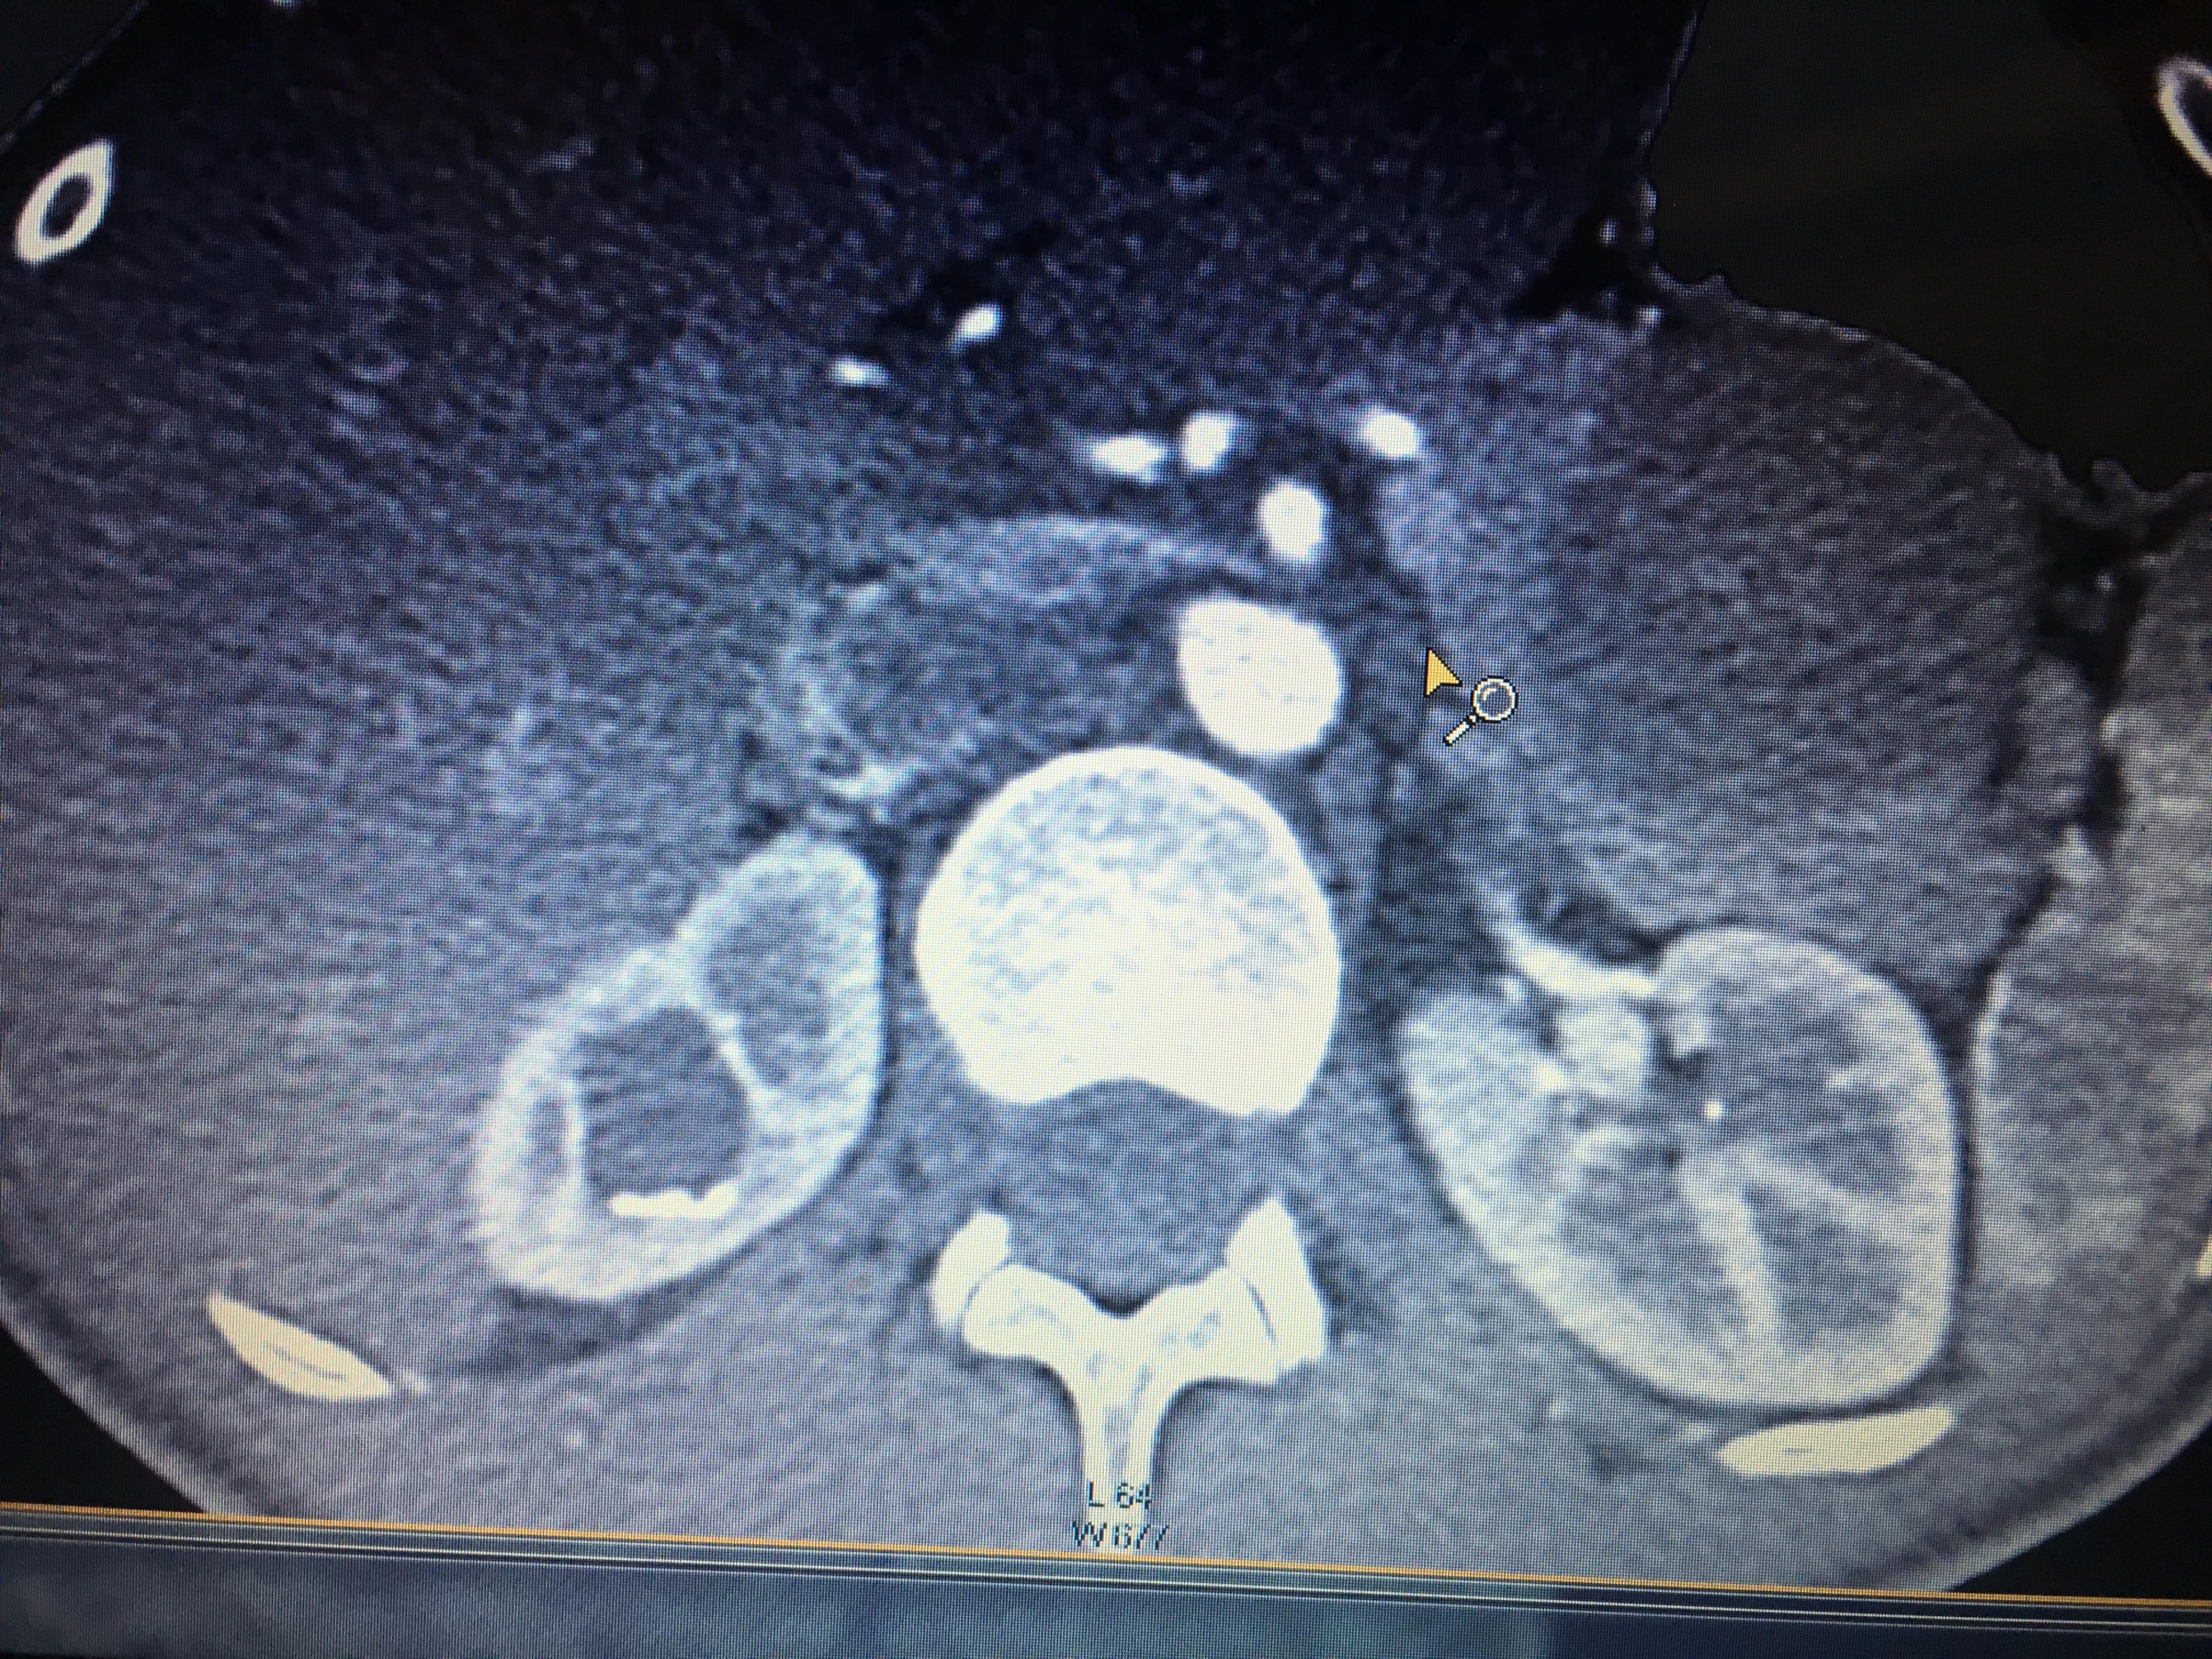

Здравствуйте,помогите, пожалуйста, с расшифровкой кт почек с контрастом. Насколько я поняла, в левой почке маленький камешек. А что за образование в правой почке? Киста с кальцинированной стенкой или камень? Спасибо за ответ!

Здравствуйте! На последнем снимке - больше данных за конкремент. Но при описании снимков должны определяться плотность образования, и нет изображения ни одного фрагмента ни одного из мочеточников. И самих снимков обычно бывает больше. Недостаточно данных для заключения.